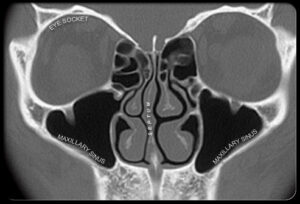

سینوس ها، حفره های هوایی در داخل سر:

سینوس ها فضاهای پر ازهوایی در داخل جمجمه شما هستند که با غشاهای مخاطی پوشیده شده اند. شما چهار سری سینوس دارید: سینوس های پیشانی در بالای چشم ها، دو سینوس فکی در پشت استخوانهای گونه دو طرف، سینوس های اتمویید: 18-22 حفره مثل کندوی عسل پشت پل بینی، سینوس های اسفنوئید پشت بینی و زیرمغز .

سینوس ها مثل اثر انگشت در هر شخص با دیگران متفاوتند.